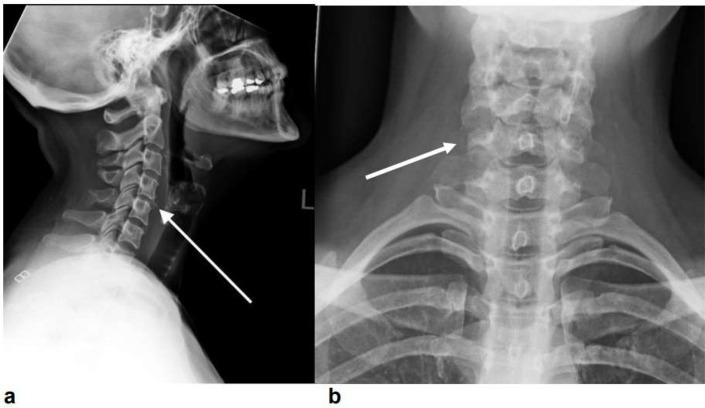

文献中描述了颈椎的几种解剖变异,从良性表现到具有不同临床意义的变异,包括与先天性疾病的关联。我们描述了一例极其罕见的颈椎解剖变异病例,该变异为颈椎C4和C5右侧横突的副关节。该病例为一名35岁女性,因间歇性钝性颈部疼痛6周就诊于初级保健机构。进行了颈椎X线检查,未显示急性骨折、脱位或椎体塌陷的影像学证据。然而,X线显示有细微的多节段前缘骨赘形成。由于不能排除轻微的粉碎性骨折或骨赘生长;患者随后进行了颈椎CT检查。结果显示C4和C5右侧横突均有副关节,这是一种极其罕见的解剖变异。我们对X线和CT成像方式结果的比较突出了利用CT识别副关节异常的重要性,这有助于指导患者接受适当的治疗。尽管在临床实践中可能见过类似病例,但据我们所知,文献中此前没有C4-5副关节的记录。